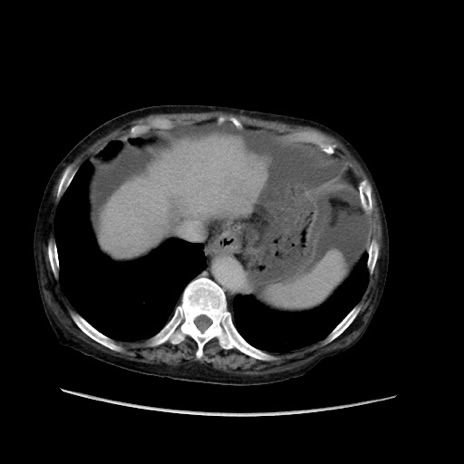

症例31(横断像)

【症例】80歳代 女性

【主訴】腹部膨満感

【現病歴】他院にて肝硬変にてフォロー中。1週間前から便秘、腹部膨満感、臍部腫瘤あり受診となる。

【既往歴】肝硬変

【身体所見】腹部膨隆あり、皮膚変化なし、疼痛なし。

【データ】WBC 4600、CRP 0.25